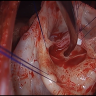

Aortic valve disease

Aortic valve replacement in patients with dextrocardia and situs inversus totalis is technically challenging, and several anatomical aspects should be considered. We present a video showing the surgical resolution of a case of dextrocardia and situs inversus totalis with severe aortic stenosis in an octogenarian patient.

In this case study, the authors demonstrate the "Y" incision and rectangular patch technique to enlarge the aortic annulus by four valve sizes and implant a size 27 Top Hat mechanical valve, as well as discuss tips and pitfalls.

A forty-two-year-old patient on hemodialysis required a redo Commando operation for recurrent infectious endocarditis. This video shows the steps the surgeon took to complete the operation.

This interesting video demonstrates a redo David I procedure for a thirty-year-old woman diagnosed with aortic insufficiency with bicuspid aortic valve. This case has the added layer of the patient also having had a PTA repair and reconstruction of right ventricular outflow track with a homograft when she was six.

Proximal aortic dissection with root involvement and aortic insufficiency can be difficult to repair; in this video, the history of reparative approaches and a potentially improved technique involving aortic ring annuloplasty are presented.